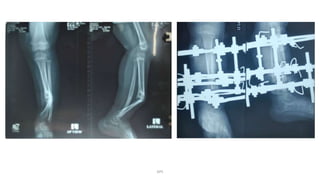

Nonunion

DPS